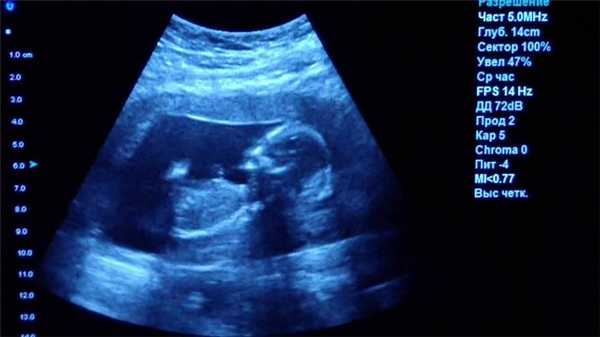

Ультразвуковое исследование (УЗИ)

Главное преимущество такого способа исследования — безопасность. УЗИ можно делать даже беременным женщинам, кроме того, приборы УЗИ-приборы мобильны, их легко можно поставить в палате пациента, чтобы наблюдать за состоянием органов и кровотока в режиме реального времени.

Однако УЗИ не может обеспечить картинку высокой чёткости, поэтому использование этого метода исследование ограничено, например, при помощи УЗИ нельзя диагностировать заболевания ЖКТ.

УЗИ - классический метод, который дает огромное количество информации, к тому же абсолютно безопасный. Сейчас он часто используется как дополняющий к другим более «тяжелым методам диагностики». Очень многое зависит от аппарата и врача, который проводит исследование. Высококвалифицированный специалист ультразвуковой диагностики на аппарате последнего поколения действительно может заподозрить опухолевый процесс на самой начальной стадии. Но окончательный онкологический диагноз ставится только по гистологическому заключению. Для этого хирург должен взять образцы ткани «подозреваемого» органа, а морфолог посмотреть, то что происходит в клетках ткани. В будущем, возможно, мы сумеем достичь уровня диагностики, сравнимого с гистологией, и без хирургического вмешательства. Но пока это только будущее.

Прежде всего лучевая нагрузка есть не во всех методах. В УЗИ или МРТ не используется ионизирующее излучение, эти методы можно назвать безвредными, и проводить такие исследования в принципе можно сколько угодно. На всякий случай мы не назначаем МРТ беременным женщинам в первом триместре, но при необходимости назначаем во втором и третьем.

Что покажет УЗИ

Ультразвуковое исследование или УЗИ - это широко распространенный вид обследования, активно применяемый в диагностических центрах СПб. В ходе данной процедуры диагностика проводится с помощью ультразвуковых волн. Проходя через границы тканей различной плотности, ультразвук по-разному отражается от них. Ультразвуковая установка имеет датчик, который посылает ультразвуковой сигнал, а затем фиксирует ответ и переводит его в графическое изображение. Таким способом врачи могут хорошо обследовать:

- органы малого таза;

- органы брюшной полости;

- лимфоузлы и молочные железы;

- мягкие ткани;

- сосудистую систему.

К сожалению, серьезным препятствием для ультразвука являются кости, через которые сигнал пробиться не может. Поэтому малоинформативным является

- УЗИ головного мозга

- УЗИ сердца

- УЗИ органов средостения

- УЗИ позвоночника.

Основным достоинством УЗИ является отсутствие каких-либо противопоказаний и ценовая доступность. По диагностической ценности и точности УЗИ безусловно уступает МРТ и КТ, однако является приоритетным профилактическим и скрининговым методом обследования для многих заболеваний, включая патологии мочеполовой системы у мужчин и женщин, рака молочных желез и органов брюшной полости, воспалений мягких тканей.